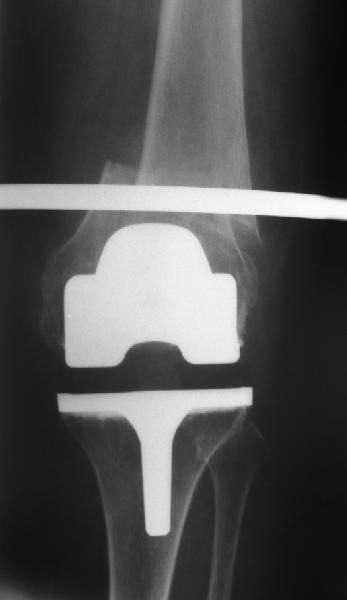

Re: перипротезный перелом

То, что планируется - наиболее распространенный подход. Еще менее инвазивный вариант - закрытый антеградный интрамедуллярный остесинтез. Мы используем гвозди, которые выпускаются предприятием ЦИТО, т.е. недорогие. Там в дистальное отверстие можно ввести 3 винта (2 снаружи и один навстречу), еще и угловая стабильность получается.

Александр Николаевич, сколько у вас таких клиентов? Каковы исходы? Только ли ЦИТОвские стержни использовали? Были ли с неправильно сросшимися переломами? У меня есть 2 клиента. Только переломы срослись у одного с вальгусом у другого с варусом. Планирую ту же схему через остеотомию.